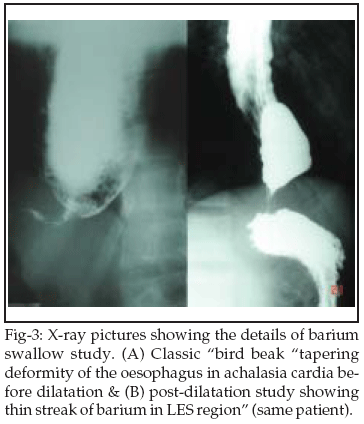

The balloon catheter needs to be held by the technician at the mouth guard to prevent its distal migration during air insufflation. We suggest "EASL" as a safer and an equally effective alternative to fluoroscopic assessment of dilatation of the LES. On looking at the LES from above, if the balloon walls run parallel and meet the stretched LES at right angles, the balloon "waist" is surely obliterated and the dilatation force is usually effective (Figure-2A): the dilatation of LES is likely to be inadequate if the balloon walls appear to converge at the LES (Figure-2B). "EASL" permits full distension of pneumatic balloon even without the use of a pressure guage. If parallel balloon walls continue to meet the stretched LES at right angles, further expansion may result in balloon rupture. Thus "EASL" can impart near-accurate information about effacement of the balloon "waist" and adequacy of LES dilatation. When combined with history of subjective improvement, "EASL" can surpass the need for serial LES manometry and radionuclide transit studies.23 However, we support the indication of an early post-operative contrast study to exclude oesophageal leak or perforation.24 Dilatation trauma to the LES results in muscle spasm in a zone with high resting pressures. Therefore, post-treatment flow of barium across the LES may not be apparent within 24 hours in spite of significant subjective relief.25 An early re-dilatation should be withheld in such cases. We encountered this situation in three (12%) patients. In our opinion, replacement of the classic "bird beak" deformity (Figure-3A) by a thin streak of barium (Figure-3B) or appearance of longitudinal folds within the LES region (Figure-4) indicate significant radiological improvement.